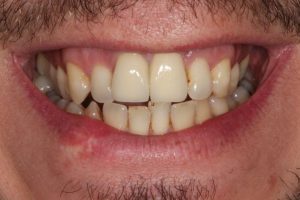

This patient had broken their upper front tooth and the exisitng dental crown had fallen off. The underlying root was unfortunatley irreparable.

The dental root was subsequently removed and an implant placed at the same time. The implant had a temporary crown placedon the same day.

The ‘After’ photos shows the final crown that was made after 3 months. The implant crown was made to match the form and colour of the exisiting teeth to give an overall natural aesthetic finish.